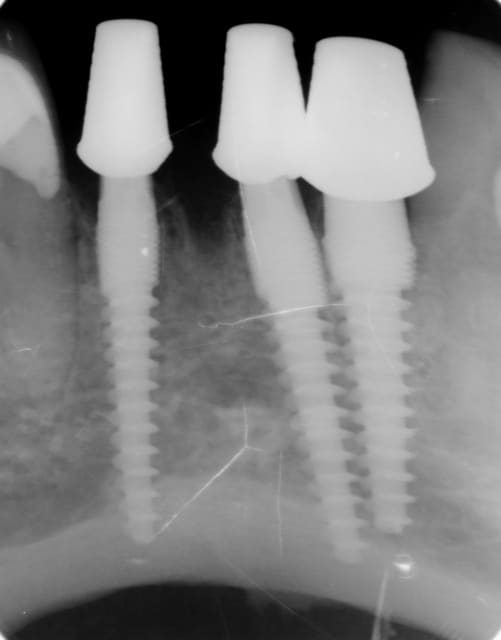

Pour la distance inter-implants c est une bonne remarque, le distance réglementaire est de 2/3mm en méthode conventionelle , ici c´est une variante du flapless en forant de manière à condenser l´os via un foret à 3 faces. En préservant le périoste on a remarqué que cette distance réglementaire pouvait être plus petite. C est une observation , qui marche (en flaples) dans ma pratique et dans celles de mes confrères Allemands, à ma connaissance pas enormément documenté . Ceci dit il y a un livre en francais qui en parle "implantologie flapless" de Byung Ho Choi et wilfried Engelke (Pr de Göttingen).

Sur le cas posté au début la dernière radio est après deux ans post OP. Ci dessous un autre exemple.

Les 12 premières photos sont un même cas avec implantation immédiate.

Le deuxième cas c est les photos 13 14 15 , (la photo 14 et 15 est après 5 ans)

Le dernier cas (3 dernieres photos), a été realisé il y a 5 ans il n y a pas de problème, je ne trouve pas les radios malheureusement je vais chercher encore un peu dans la journée.